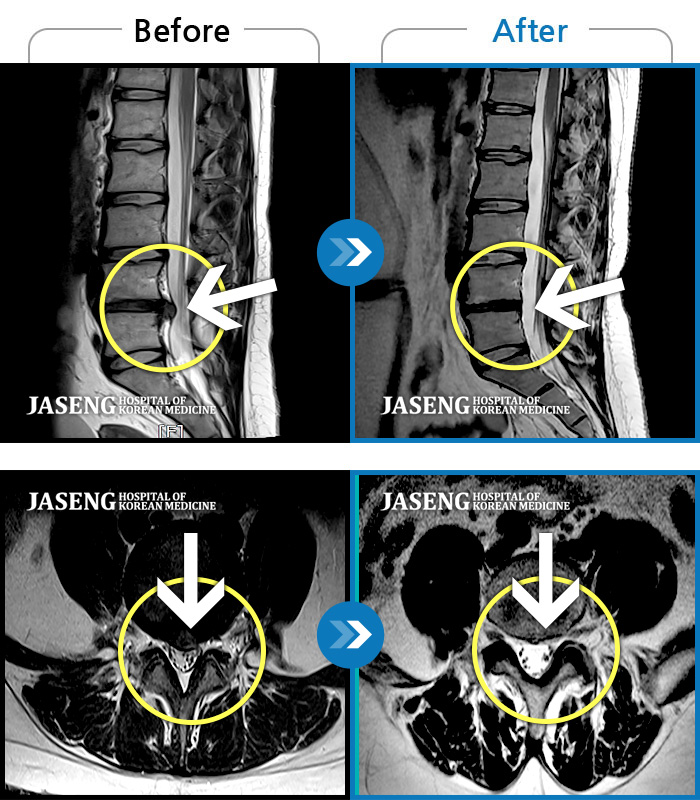

허리디스크

해운대 · 김상돈 원장

허리 골반 통증이 있고 허리를 숙일 때 불편합니다.

촬영시기

2020.09.14 ~ 2025.07.09

2025.07.11